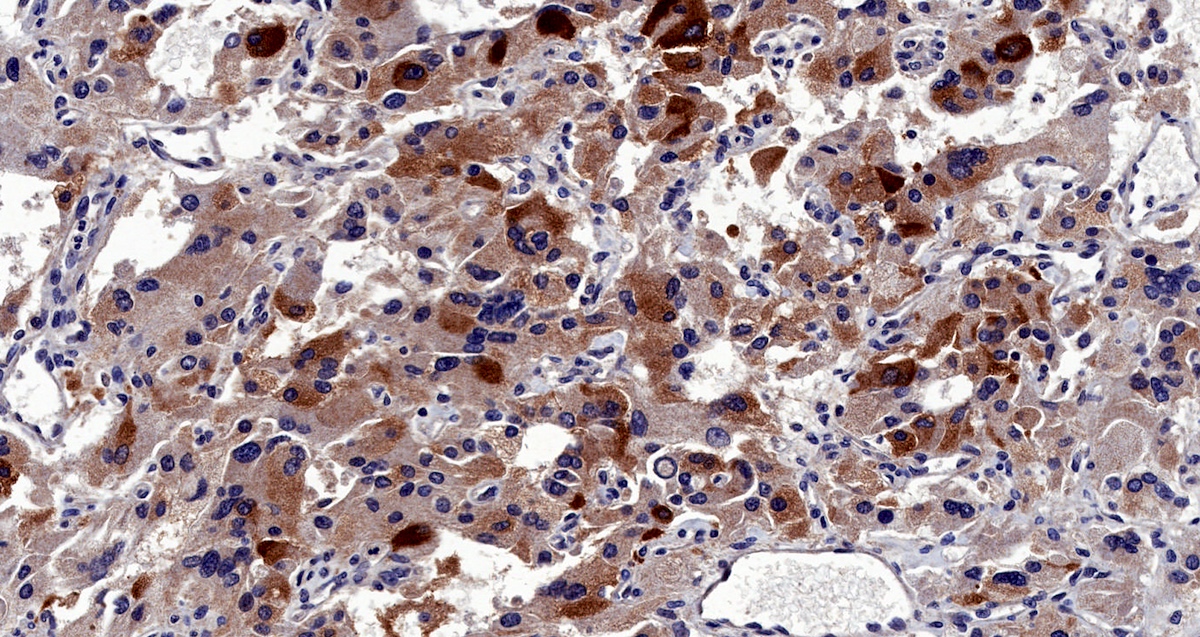

Microscopic (histologic) images

Contributed by Luvy Delfin, M.D. and Sylvia L. Asa, M.D., Ph.D.

Microscopic (histologic) description

- Prevailing histologic pattern: epithelioid chief cells arranged in distinctive clusters / nests (zellballen pattern), separated by prominent fibrovascular stroma (J Clin Med 2018;7:280)

- Trabecular pattern: ribbons or cords of epithelioid cells divided by fibrous bands

- Other patterns: pseudorosette, angioma-like, spindled and sclerosing

- Chief cells: round, oval to polygonal cells with abundant granular basophilic, eosinophilic or amphophilic cytoplasm (Surg Pathol Clin 2019;12:951)

- Intracytoplasmic hyaline globules may be present in sympathoadrenal paragangliomas

- Giant multinucleated cells and bizarre cells can be present (Srp Arh Celok Lek 2002;130:7)

- Rarely, elongated and spindle shaped cells with a sarcomatoid appearance may be found

- Scattered ganglion cells can be seen

- May have nuclear atypia

- May have dysmorphic vessels, melanin-like pigment (neuromelanin) (pigmented paraganglioma), amyloid, abundant stroma and osseous metaplasia (Diagn Pathol 2012;7:77, Hum Pathol 1992;23:33)

- No or rare mitotic figures except in highly aggressive rapidly proliferating lesions

- May have focal chronic inflammatory infiltrate

- Necrosis is unusual except in patients who have undergone preoperative tumor embolization

- Special histopathologic features usually related to genetic syndromes:

- VHL syndrome: prominent stromal edema, clear cytoplasm and lipid degeneration (Am J Surg Pathol 1987;11:480)

- SDHx related syndrome: granular eosinophilic cytoplasm (Am J Surg Pathol 2020;44:422)

- MEN2 syndrome: unilateral or bilateral adrenal medullary hyperplasia (Neoplasia 2014;16:868)